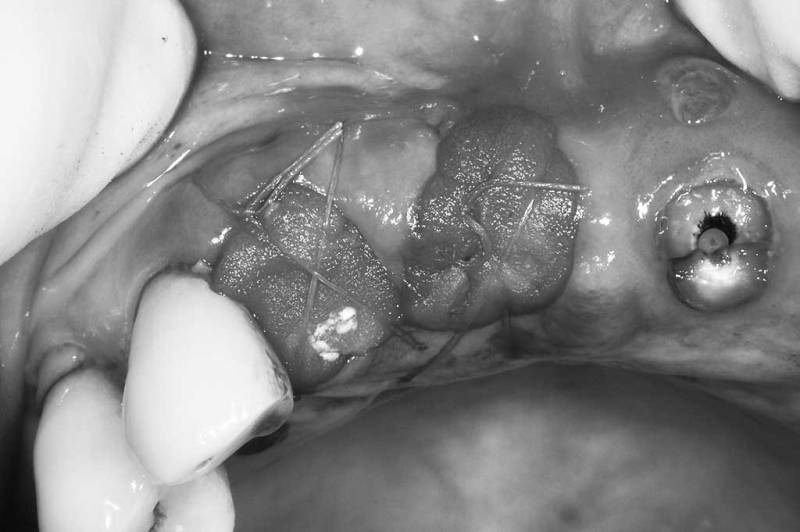

窩洞保存術術中